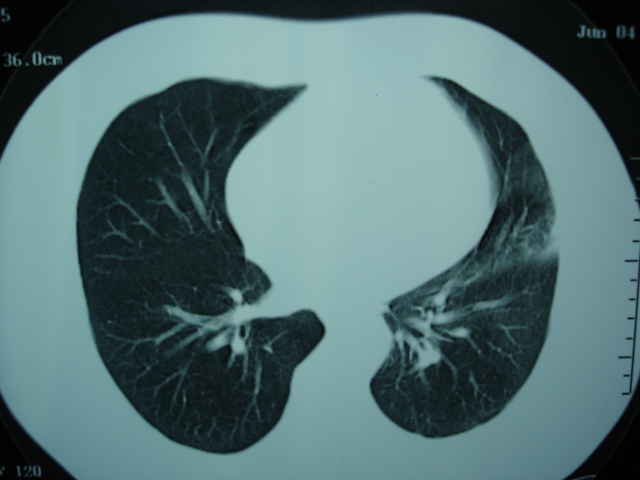

第一次ct2009.6.4